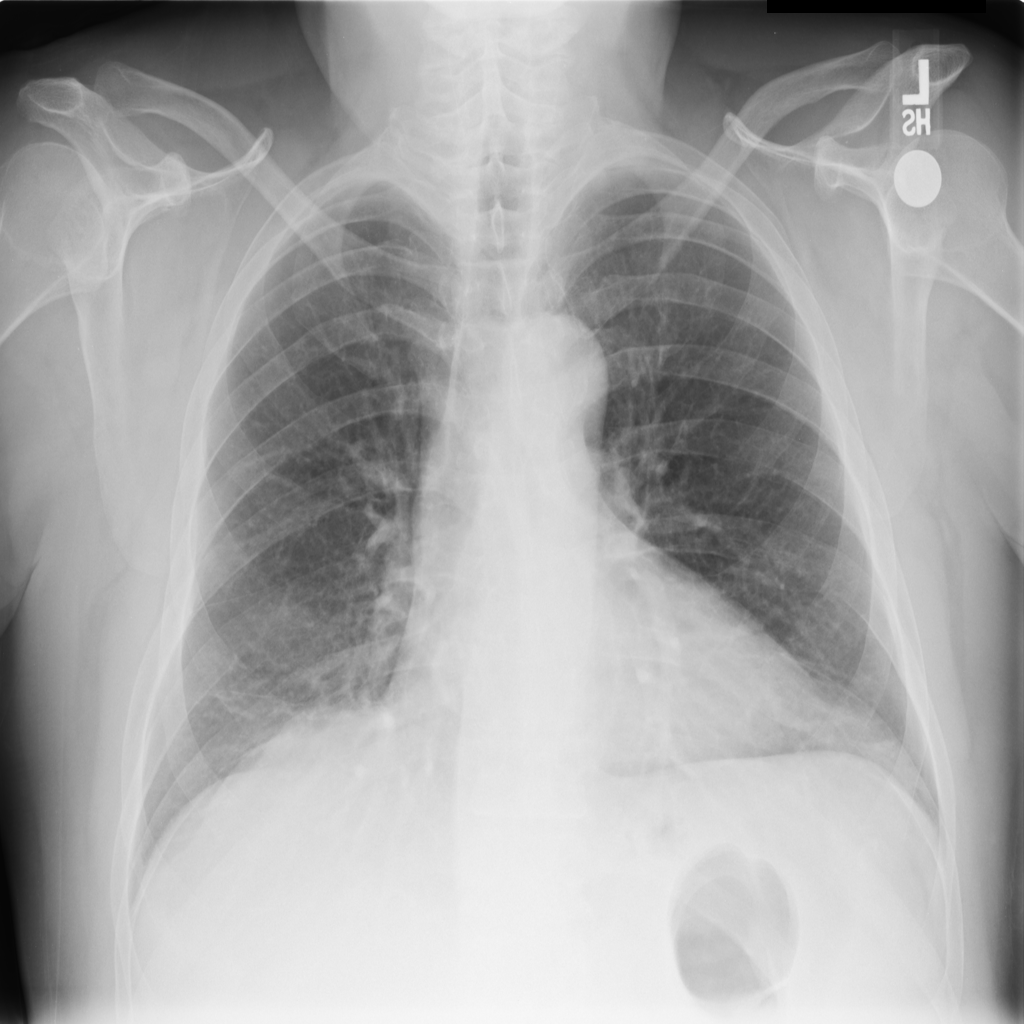

PAT-B733 · IMG-000Consolidation

PAT-B733 · IMG-000

PA